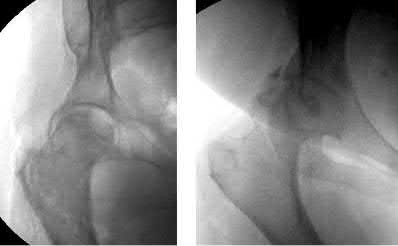

A 12-year-old obese male presents with a stable slipped capital femoral epiphysis (SCFE) of the left hip. Which of the following factors is the strongest indication for prophylactic in situ pinning of the asymptomatic contralateral right hip?

Options:

- Body Mass Index greater than the 95th percentile

- Slip angle greater than 50 degrees on the affected side

- Age greater than 14 years at presentation

- Presence of an underlying endocrine disorder (e.g., hypothyroidism)

- Male gender

Correct Answer: Presence of an underlying endocrine disorder (e.g., hypothyroidism)

Explanation:

Prophylactic pinning of the contralateral hip in SCFE is controversial but is strongly indicated in patients with a high risk of bilateral involvement. Risk factors predicting contralateral slip include an underlying endocrine disorder (such as hypothyroidism, panhypopituitarism, or renal osteodystrophy), prior radiation therapy, or age of presentation less than 10 years (or low modified Oxford bone age score).